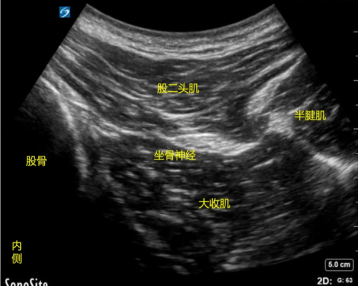

超声引导下神经阻滞镇痛术(五)

超声引导下神经阻滞镇痛术是一种有效治疗各种慢性疼痛的主要手段。广泛应用于颈源性疼痛、癌痛、腰背部疼痛、神经卡压性疼痛等的治疗。神经阻滞是指在神经干、丛、节的周围注射镇痛消炎药,阻滞其冲动传导,使所支配的区域产生镇痛作用。神经阻滞只需注射一处,即可获得较大的区域良好镇痛效果。

超声引导下神经阻滞镇痛术优点:

1.安全性:超声图像可看到神经、血管、胸膜和其他组织,以及穿刺针和镇痛消炎药扩散,从而避免损伤神经、误穿血管和胸膜等严重并发症;

2.直观性:超声图像可直接看到神经及其相邻结构,能克服解剖变异带来的穿刺困难,提高穿刺成功率和麻醉镇痛质量;

3.速效性:超声引导穿刺针更接近神经,而且可以多点注射和观察局镇痛消炎药的扩散,可缩短镇痛药物起效时间、降低药物用量。